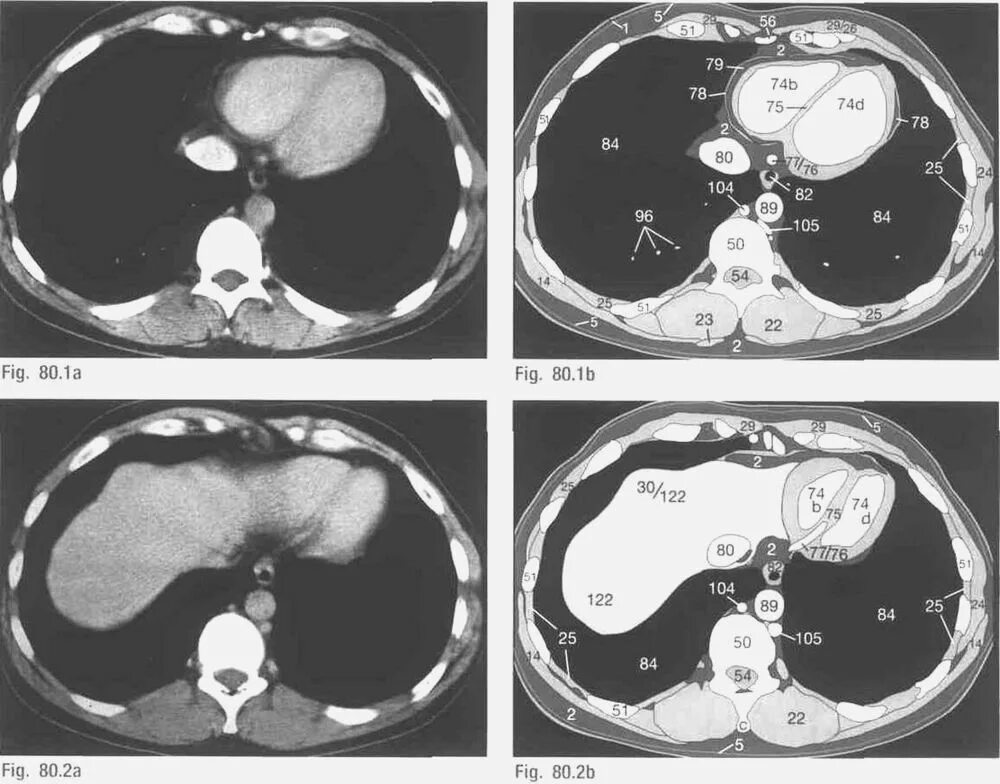

Показатель кт